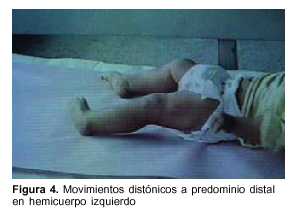

Lactante de 1 año, raza blanca, sexo femenino, con antecedentes familiares de padres consanguíneos (parientes tres grados aparte). Producto de primera gestación, embarazo normal, parto de término. Peso al nacer 4.500 g, longitud 53 cm, perímetro cefálico 35 cm. Test de Apgar 6/8. Buen crecimiento y desarrollo (figura 2). Comienza su enfermedad dos días después de una enfermedad diarreica aguda, caracterizada por trastorno de conciencia, crisis convulsiva generalizada tónica y movimientos anormales bucolinguofaciales y de las extremidades. El examen físico al ingreso mostró: perímetro cefálico 47 cm, peso 10.200 g, longitud 80 cm. Sin alteraciones morfológicas, vigil, hiporreactiva, movimientos anormales espontáneos caracterizados por discinecias bucolinguofaciales (figura 3) y movimientos distónicos a predominio distal en hemicuerpo izquierdo (figura 4). Hipotonía axial severa, sin sostén cefálico ni sedestación e hipertonía espástica, hiperreflexia, clonus y Babinski bilateral a predominio derecha.

Nuestra paciente se presenta con la forma clásica de AGI que se inicia entre los 2 y los 37 meses de edad con síntomas agudos(6). Consiste en la aparición brusca en el curso de una infección banal, inmunización, ayuno prolongado u otra situación hipercatabólica, de síntomas neurológicos que involucran principalmente el sistema extrapiramidal, siendo el desarrollo madurativo generalmente normal hasta ese momento(3,5,6). La paciente presentó, en forma brusca, hipotonía severa, movimientos distónicos principalmente bucolinguofaciales, irritabilidad, convulsiones y alteraciones piramidales sin acidosis metabólica. La enfermedad fue interpretada inicialmente como una encefalitis. Pasado el episodio agudo se produce una mejoría incompleta persistiendo la distonía y la coreoatetosis(12,13), si bien hay descripciones de algún caso con remisión completa luego del episodio agudo(6). No es infrecuente la disfunción hepática durante la descompensación(3), como fue detectado en nuestro caso con aumento de GOT y GPT. Otra forma de presentación aguda menos frecuente de la AGI es la llamada crisis metabólica con hipoglicemia hipocetósica y acidosis metabólica que progresa como si se tratase de un síndrome de Reye y que tendría como un importante factor causal deficiencia de carnitina (c). En la AGI se produce una deficiencia secundaria de carnitina, con relación esterificada/libre frecuentemente elevada(14). En nuestro caso, al momento de la evaluación, había un discreto descenso de carnitina total con leve disminución del porcentaje de la libre.